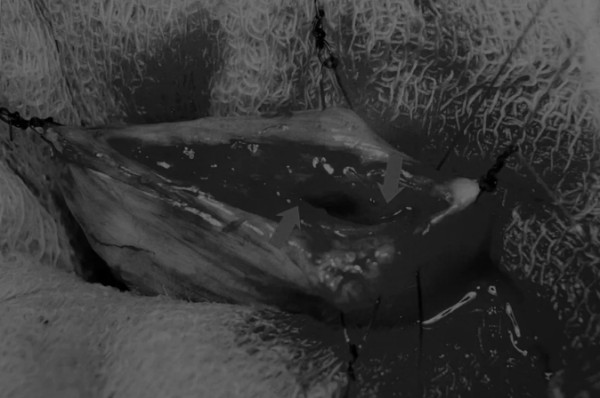

图2 在手术过程中,还需要另外两根固定缝线来保持膀胱切开术的膀胱边缘处于暴露状态

在中线开腹手术后,确定膀胱,将其取出并隔离(图1)。为了使膀胱持续暴露,可在膀胱中线两侧各放置一根固定缝线(图2)。